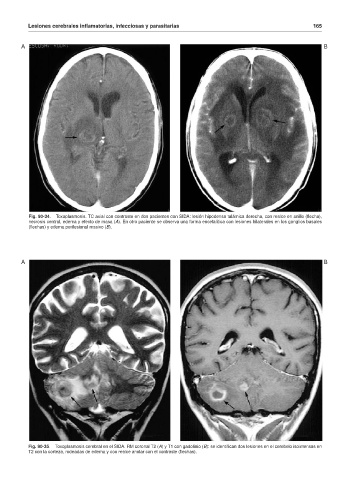

Fig. 90-34. Toxoplasmosis. TC axial con contraste en dos pacientes con SIDA: lesión hipodensa talámica derecha, con realce en anillo (flecha),

necrosis central, edema y efecto de masa (A). En otro paciente se observa una forma encefalítica con lesiones bilaterales en los ganglios basales

(flechas) y edema perilesional masivo (B).

Fig. 90-35. Toxoplasmosis cerebral en el SIDA. RM coronal T2 (A) y T1 con gadolinio (B): se identifican dos lesiones en el cerebelo isointensas en

T2 con la corteza, rodeadas de edema y con realce anular con el contraste (flechas).